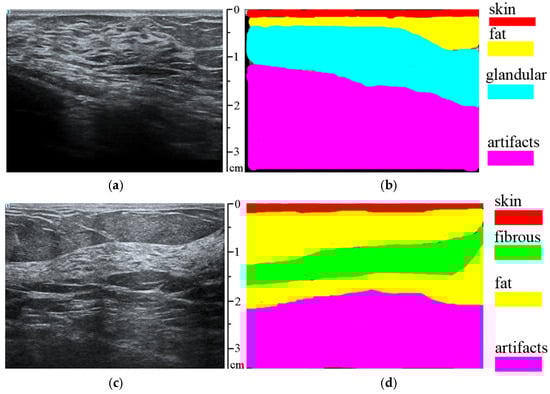

| Tissue Type | Average Percentage of Correctly Classified Tissue Pixels |

|---|---|

| Skin | 94.74% |

| Fat | 95.14% |

| Glandular tissue | 91.25% |

| Fibrous tissue | 90.21% |

| Artifacts | 86.99% |